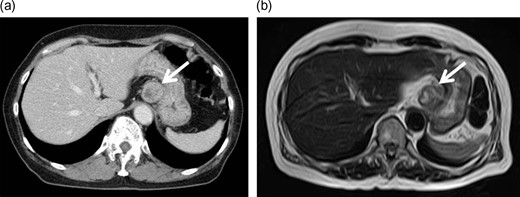

A 72-year-old Japanese woman visited our hospital for a routine health examination and underwent abdominal ultrasonography, which revealed an intra-abdominal tumor. The patient had no symptoms, and the findings of physical and laboratory tests, including carcinoembryonic antigen and carbohydrate antigen 19-9 were unremarkable. The patient had no history of previous illness and was not taking any regular medications. Contrast-enhanced computed tomography (CT) (Fig. 1a) and magnetic resonance imaging (MRI) (Fig. 1b) showed a well-defined, mildly heterogeneous solid mass of about 3 cm in diameter lying adjacent to the stomach. Endoscopy showed the lesser curvature of the stomach to be compressed extraluminally and without mucosal abnormalities (Fig. 2). An endoscopic ultrasonogram revealed a 30 × 25-mm2 low-echoic lesion that was adhered to the side of the lesser curvature of the stomach. Based on these findings, the mass was preoperatively diagnosed as a GIST of the stomach.

Enhanced computed tomography (CT) and magnetic resonance imaging (MRI). Contrast-enhanced CT (a) and MRI (b) images showed a well-defined solid mass of ~3 cm in diameter lying adjacent to the stomach, with some heterogeneity.